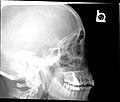

Paranasal Sinuses lat.jpg

Lateral projection of the paranasal sinuses